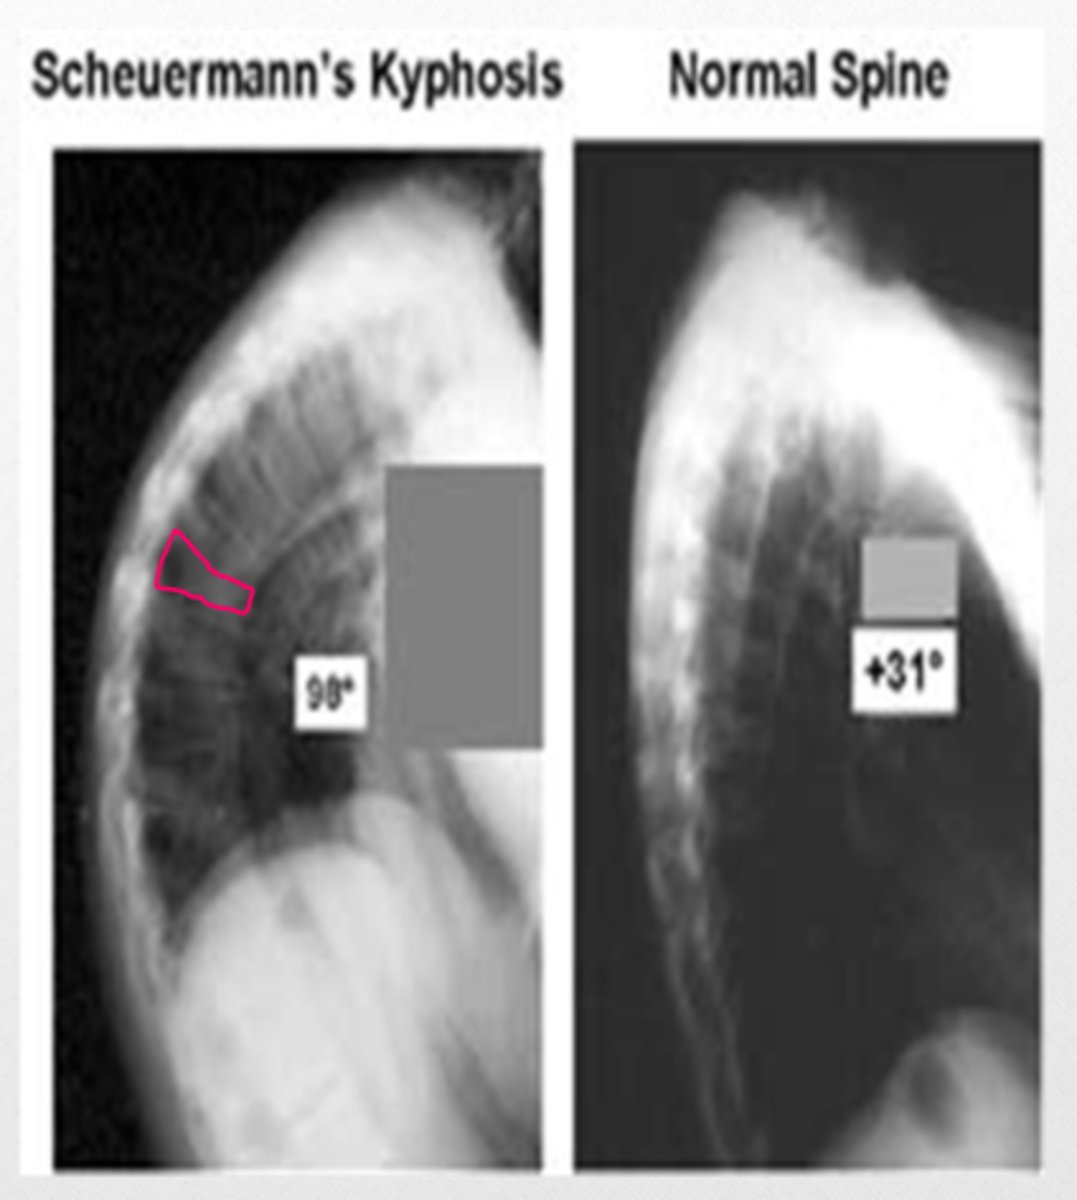

Scheuermann's disease

osteochondritis of the thoracic spine that results in wedge-shaped vertebrae

*growth disturbance of the epiphyseal plates

**accentuated thoracic kyphosis

***Schmorl's nodes

Schmorl's nodes

herniation of the nucleus pulposus through the vertebral endplate into the vertebral body

*occurs Scheuermann's disease